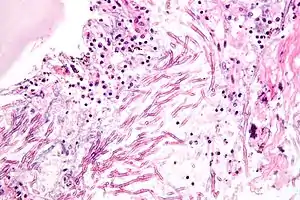

| Micrograph showing a mycosis (aspergillosis). The Aspergillus (which is spaghetti-like) is seen in the center and surrounded by inflammatory cells and necrotic debris. H&E stain. | |